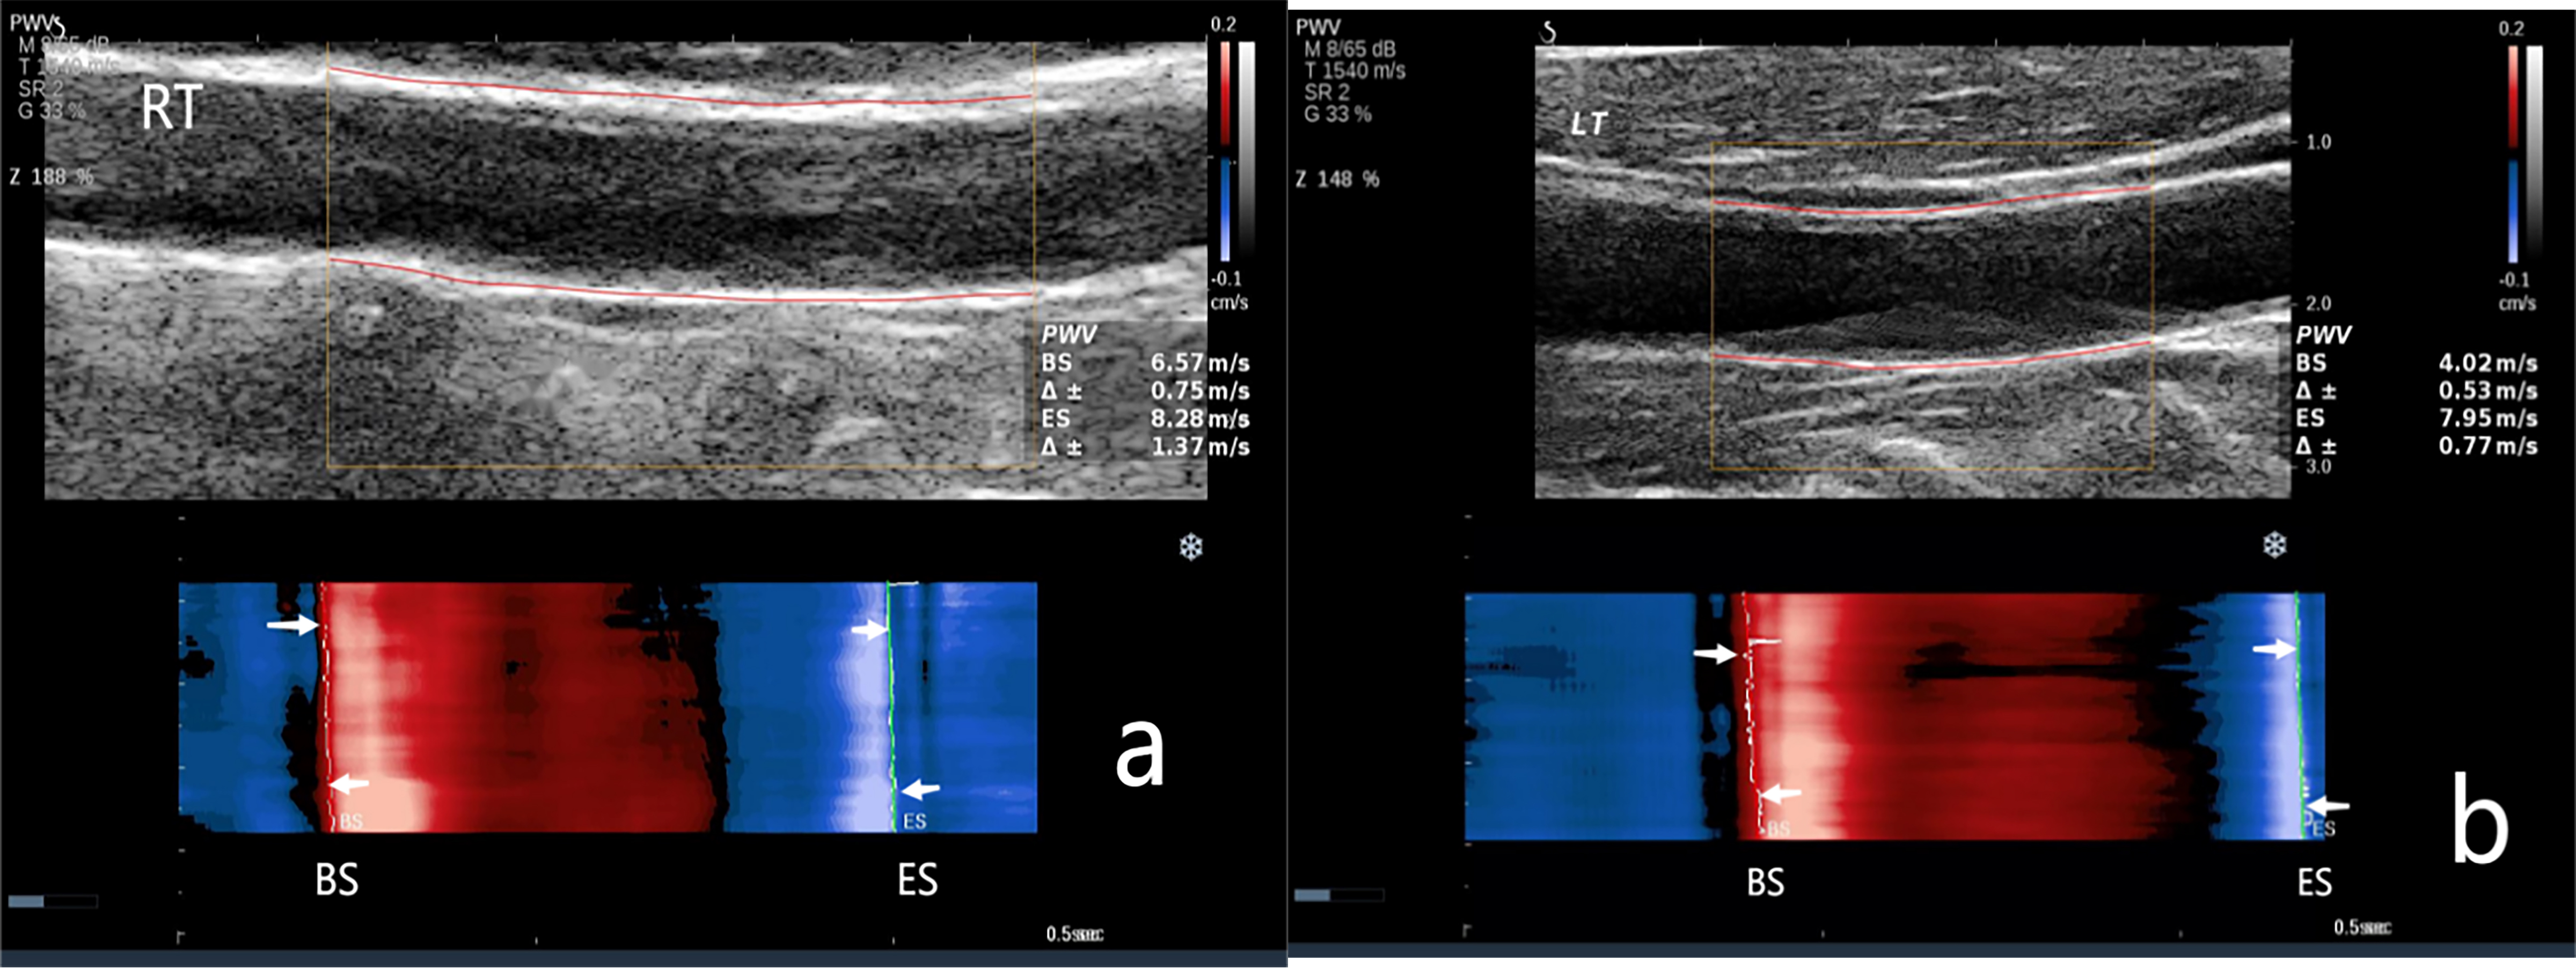

Fig. 2.

The carotid artery PWV in the Non-CAVD group. (a) PWV measurement of the right carotid artery. PWV-BS, 6.57 m/s; PWV-ES, 8.28 m/s. (b) PWV measurement of the left carotid artery. PWV-BS, 4.02 m/s; PWV-ES, 7.95 m/s. NOTE: PWV-BS corresponds to the slope of the most prominent line in the red band, whereas PWV-ES is associated with the slope of the most prominent line in the blue band. These features are highlighted in the figure by the white arrows. M, map; T, tissue tuner; SR, speckle reduction; G, gain; Z, zoom; dB, decibel; BS, beginning of systole; ES, end of systole.